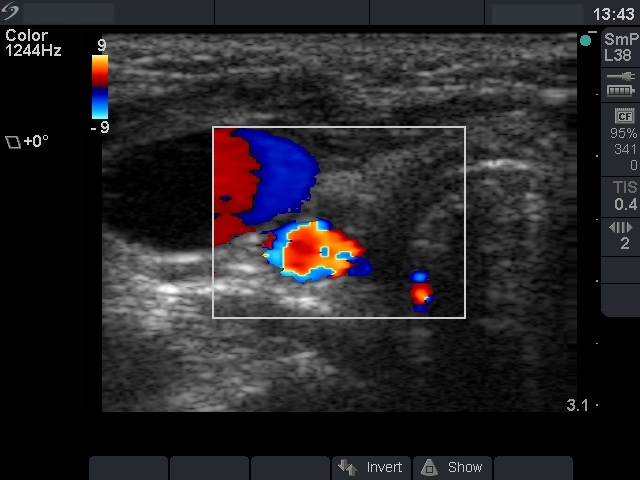

Right lobe, longitudinal scan

Right lobe, transverse scan, color Doppler mode. The tumor is avascular.